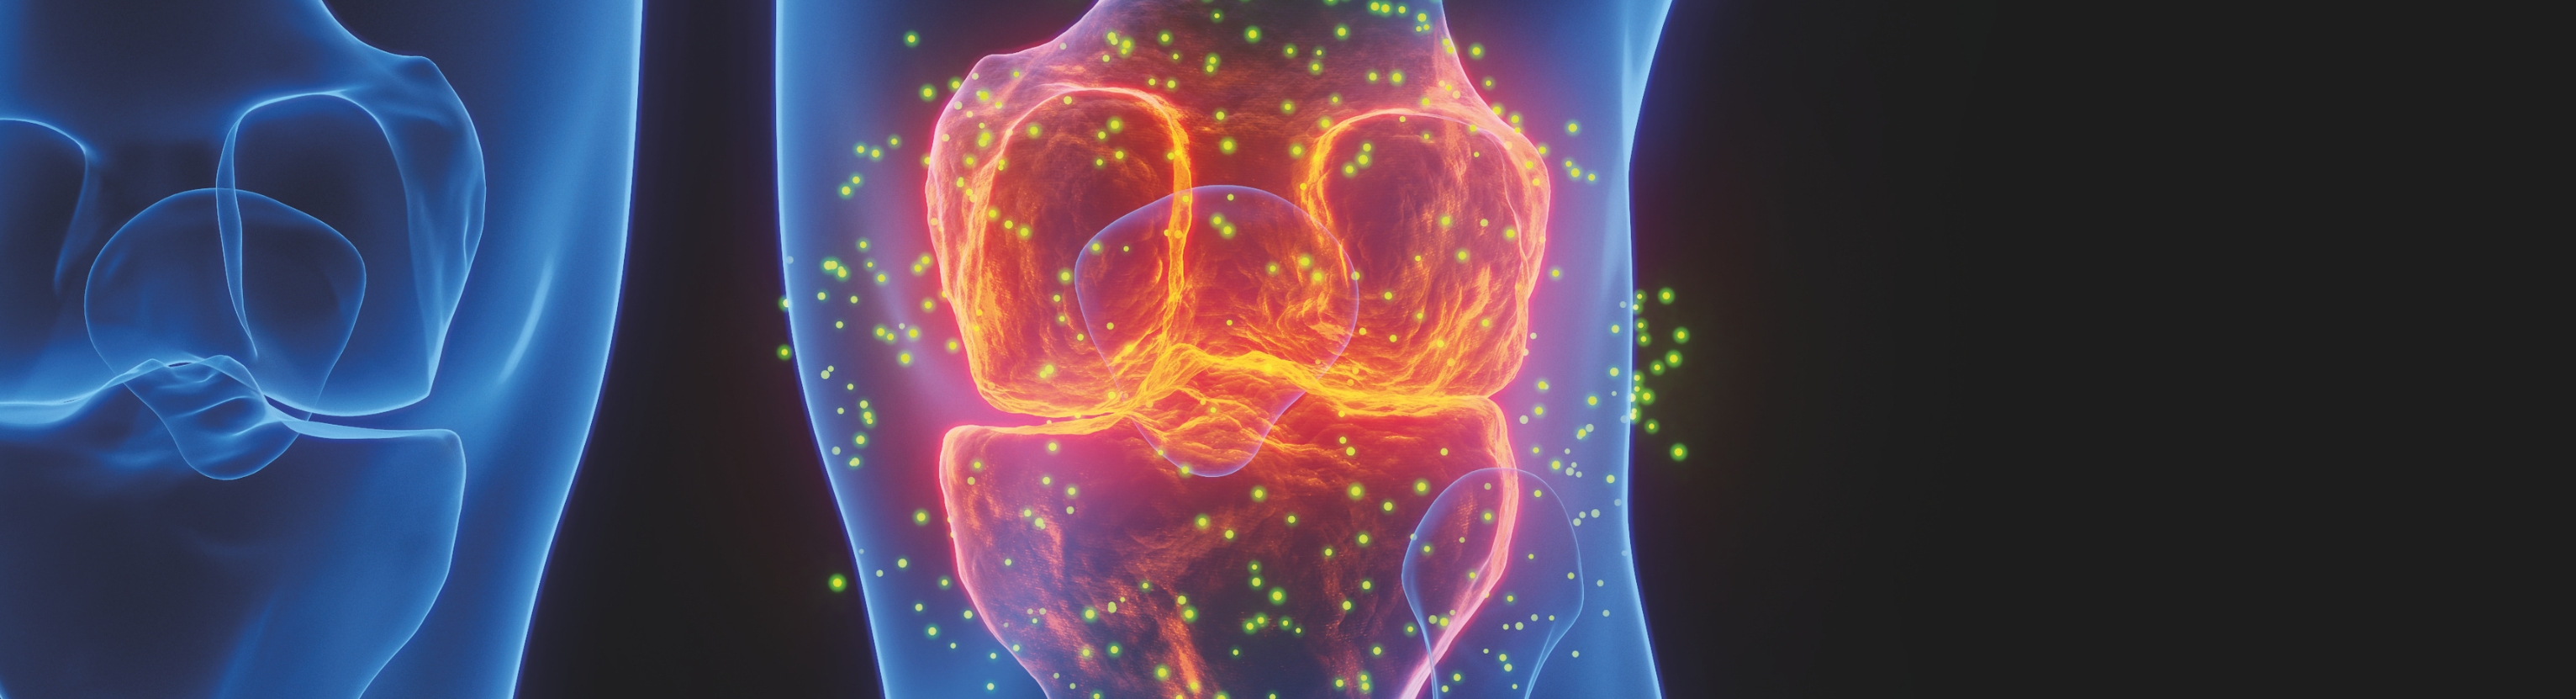

Die Transarterielle periartikuläre Embolisation ist ein minimalinvasives Verfahren mit

dem Schmerzen im Gelenkbereich bei Arthrose oder auch nach Einbau eines künstlichen Gelenks häufig gelindert werden können, wenn herkömmliche

Therapien nicht ausreichend wirksam waren. Darüber hinaus setzen wir die TAPE zunehmend auch bei anderen Erkrankungen ein, wie z. B bei chronischen Sehnenentzündungen (z. B. Tendinopathien der Schulter, Achillessehne oder des Ellenbogens). Durch den gezielten Verschluss gelenknaher Blutgefäße wird der sich selbst aufrechterhaltende Entzündungskreislauf im Gelenkbereich unterbrochen und die Bildung schmerzempfindlicher Nervenendigungen reduziert. Bereits wenige Tage nach dem Eingriff zeigt sich bei vielen Patienten eine deutliche Schmerzlinderung.